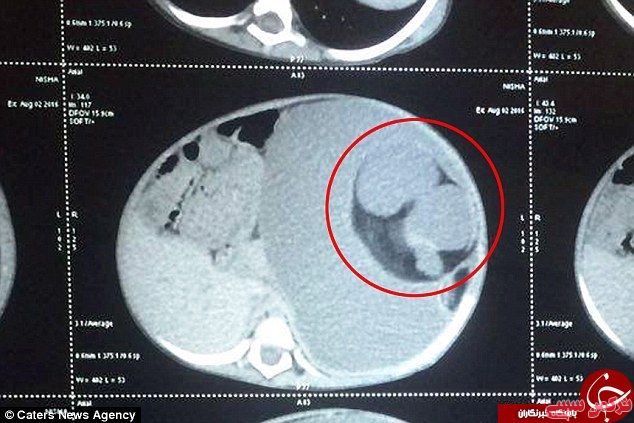

به گزارش خبرنگار ترکمن سسی به نقل از باشگاه خبرنگاران جوان،در کشور هندوستان یک دختر بچه 15 ماهه به نام نیشا به وسیله پزشکان تحت عمل جراحی قرار گرفته و از معده او دو جنین تکامل نیافته به اندازه دو توپ تنیس خارج شده است.

این جنین ها در واقع دو قلوهای همراه نیشا بوده اند که در یک پدیده عجیب که تنها 200 مورد از آن تا به حال در دنیا شناسایی شده است به جای رشد در رحم مادر درون یکی از جنین ها بزرگ می شوند.به دلیل نقص ژنتیکی شدید تکامل آنها تا 9 ماهگی کامل نشده و تنها پس از تولد نیشا با استفاده از بند ناف از او تغذیه کرده و بافت سلولی آنها افزایش یافته است.

این بیماری به نام foetus in fetu بسیار نادر است و معمولاً در بدن مادری که بارداری چند قلویی را پشت سر گذاشته مشاهده می شود، در این اختلال اجزایی چون پوست، گوشت، مو، استخوان و کلسیم به صورت ناقص در بدن شکل می گیرند.

پزشکان در ابتدا تصور می کردند که یک توده سرطانی در بدن نیشا در حال رشد است اما پس از اسکن از شکم او دریافتند که دو قلو های انگلی در بدن او تشکیل و در حال استفاده ازخون و منابع غذایی بدن او هستند.

پزشکان در یک عمل جراحی 2 ساعته موفق به خارج کردن دوقلوهای انگلی شده اند که به اعضایی چون پانکراس، کلیه و معده کودک وصل شده بودند.